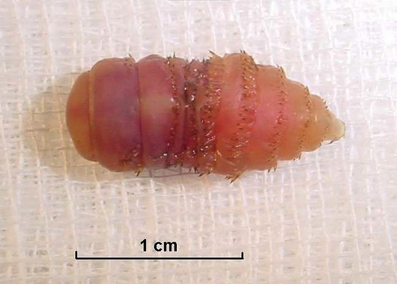

▼4.57隻蛆蟲在一名92歲的婦人耳朵中存活了長達三天的時間,她卻完全沒感覺…這就是奶奶們耳朵不好的原因嗎?